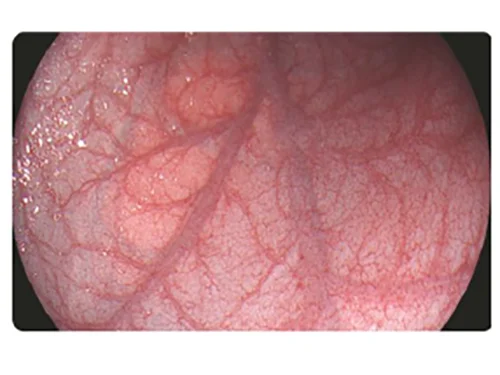

Белый свет

Белый свет

Белый свет

Белый свет